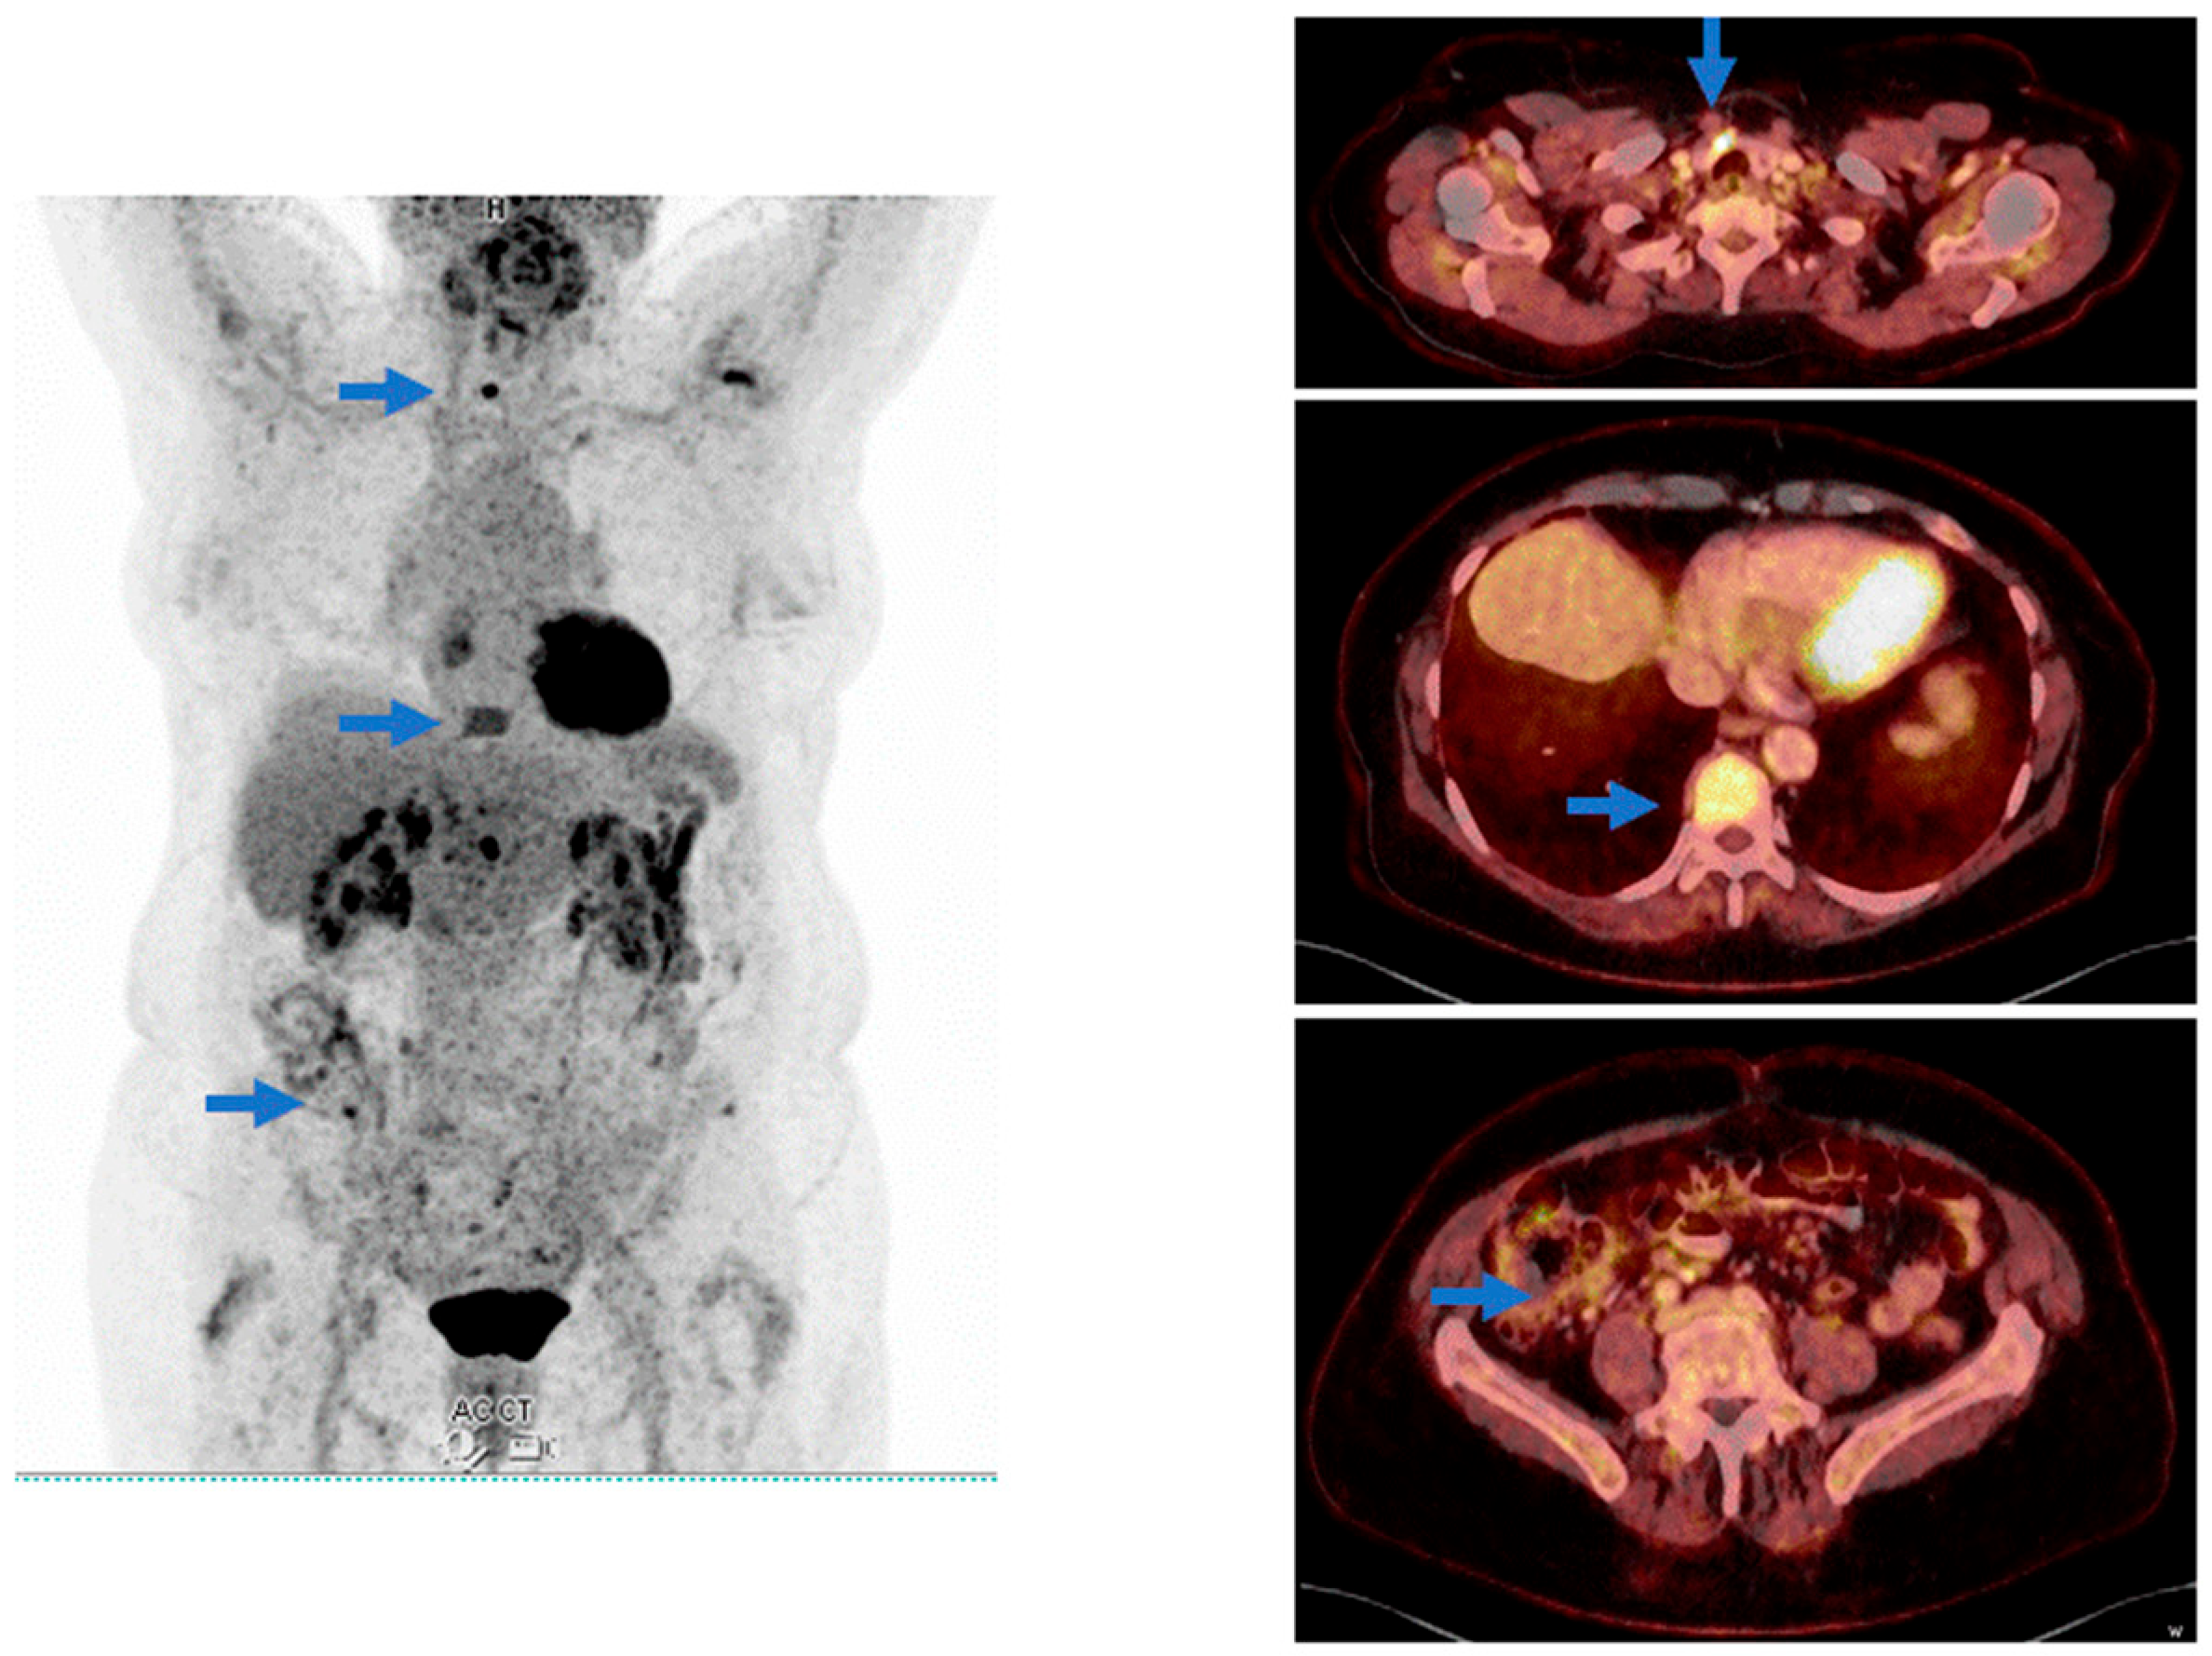

Mild SARS-CoV-2 Infection with the Omicron Variant Mimicking Metastatic Cancer on Whole-Body 18-F FDG PET/CT Imaging

2. Case Presentation